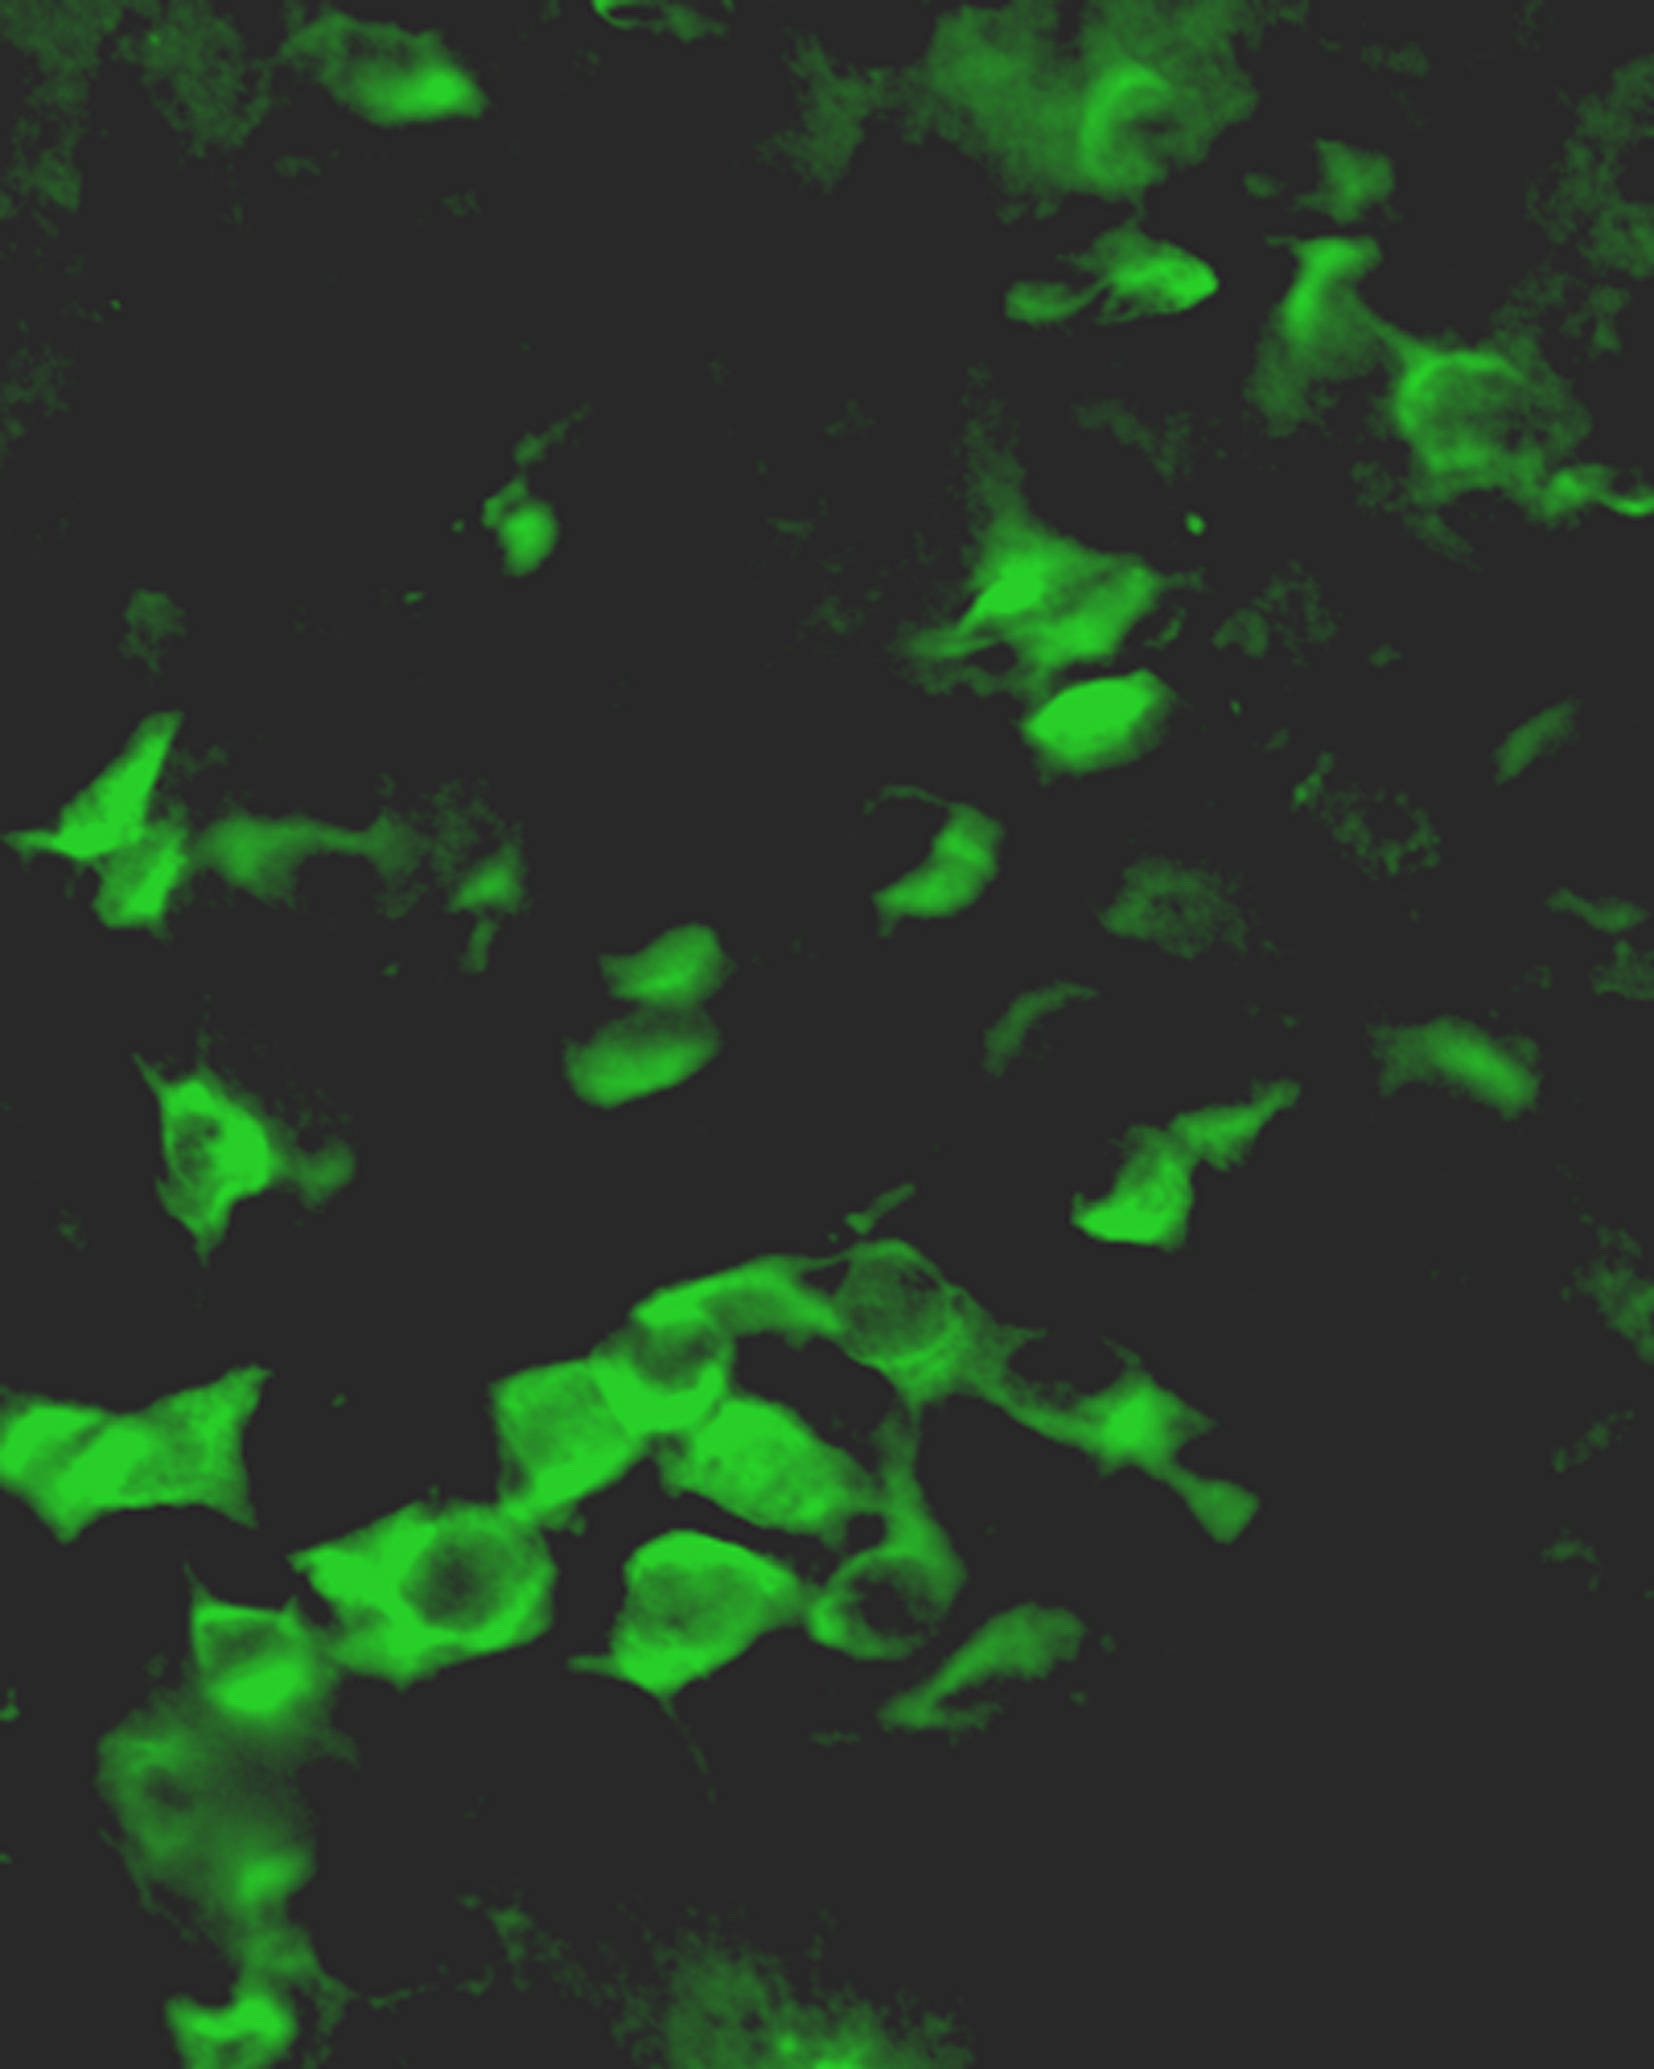

Nanoparticles developed at UB allow cells on the floor of a mouse brain ventricle to express the gene for green fluorescent protein.

"What we did here instead was to reactivate adult stem cells located on the floor of brain ventricles, germinal cells that normally produce progeny that then die if they are not used," said Michal K. Stachowiak, Ph.D., co-author on the paper and associate professor of pathology and anatomical sciences in the UB School of Medicine and Biomedical Sciences. Stachowiak is in charge of in vivo studies at the UB Institute for Lasers, Photonics and Biophotonics.